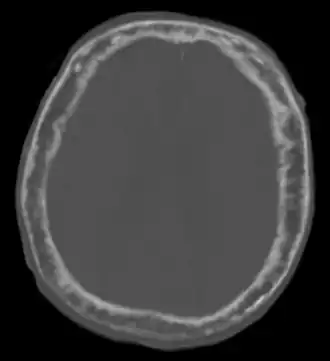

Description de cette image, également commentée ci-après

« Ce patient (homme, 92 ans) présentait une hémiparésie. Un épaississement de la boîte crânienne a été incidemment découvert, faisant évoquer la maladie osseuse de Paget »

Elle est caractérisée par l'hypertrophie et la déformation de certaines pièces osseuses, principalement le bassin (près des 3/4 des atteintes), le crâne (40 % des atteintes), le rachis lombaire (près de la moitié des atteintes) et les os longs[4]. On peut retrouver des signes vasomoteurs, tels qu'une chaleur, une rougeur de la peau sus-jacente.